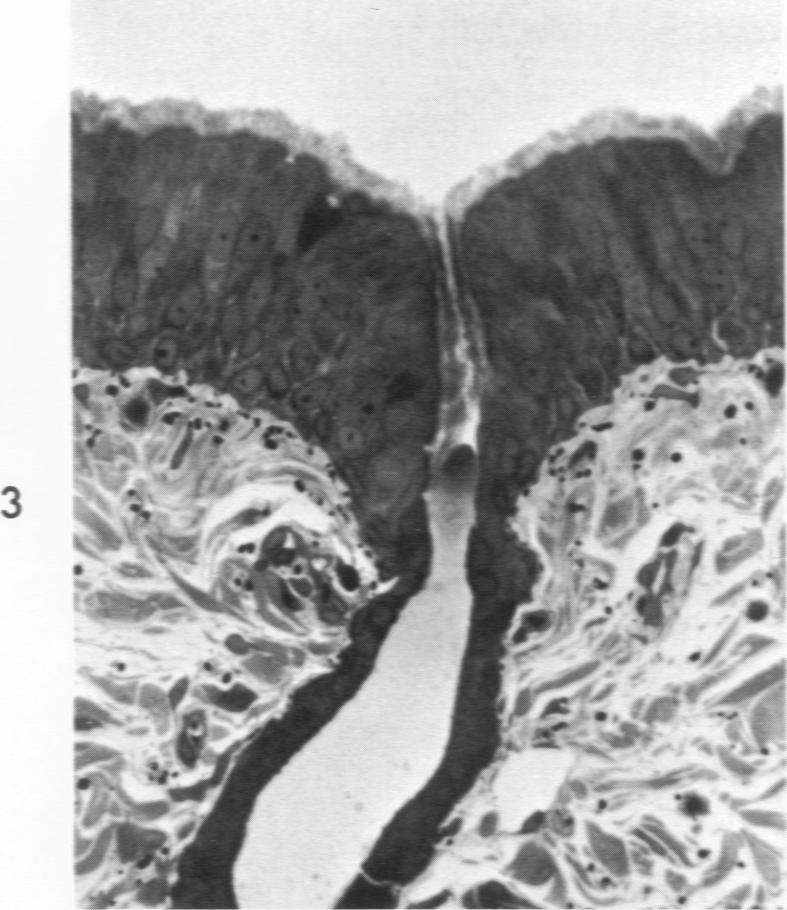

支气管腺开口处的鳞状化生。

Squamous metaplasia of the opening of bronchial glands.

The major bronchi of swine, a dog and rabbits were examined with a scanning electron microscope and the fine structure of the openings of bronchial glands were studied three-dimensionally. The smallest areas of squamous metaplasia involved the duct openings. By examining serial sections with the light and transmission electron microscopes these early lesions were found localized at the opening of the bronchial gland duct. Cells intermediate to goblet and squamous cells were present in these lesions. Squamous metaplasia starting at this particular location is probably common and metaplasia can be an intracellular process.

用扫描电子显微镜检查了猪、狗和兔子的主支气管,并对支气管腺开口的精细结构进行了三维研究。鳞状化生面积最小的区域涉及导管开口。通过光学显微镜和透射电子显微镜检查连续切片,发现这些早期病变局限于支气管腺导管开口处。在这些病变中存在介于杯状细胞和鳞状细胞之间的细胞。从这个特定位置开始的鳞状化生可能很常见,并且化生可能是一个细胞内过程。